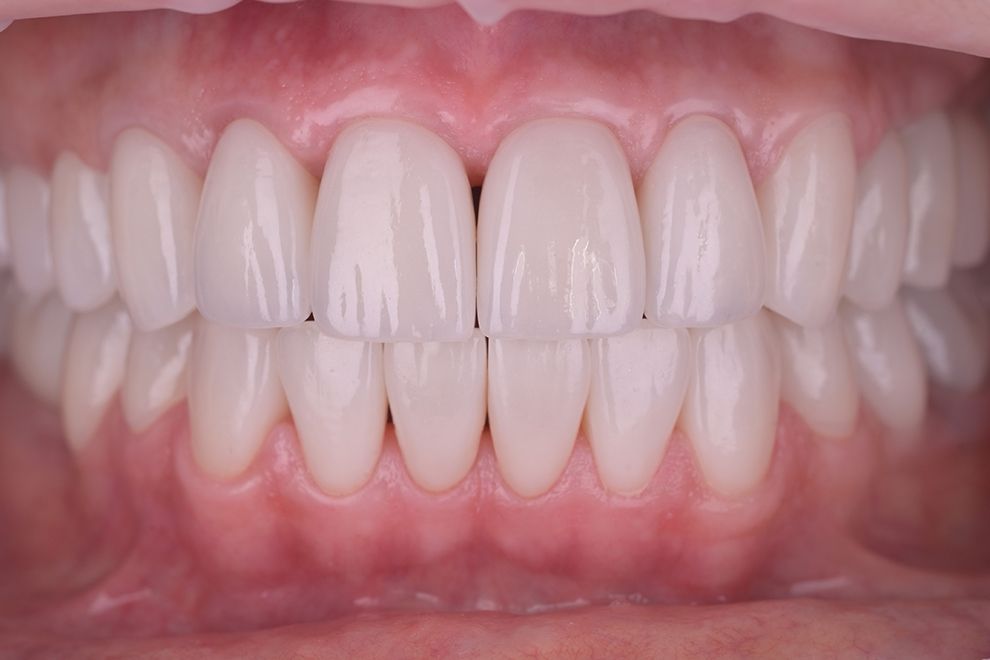

до и после